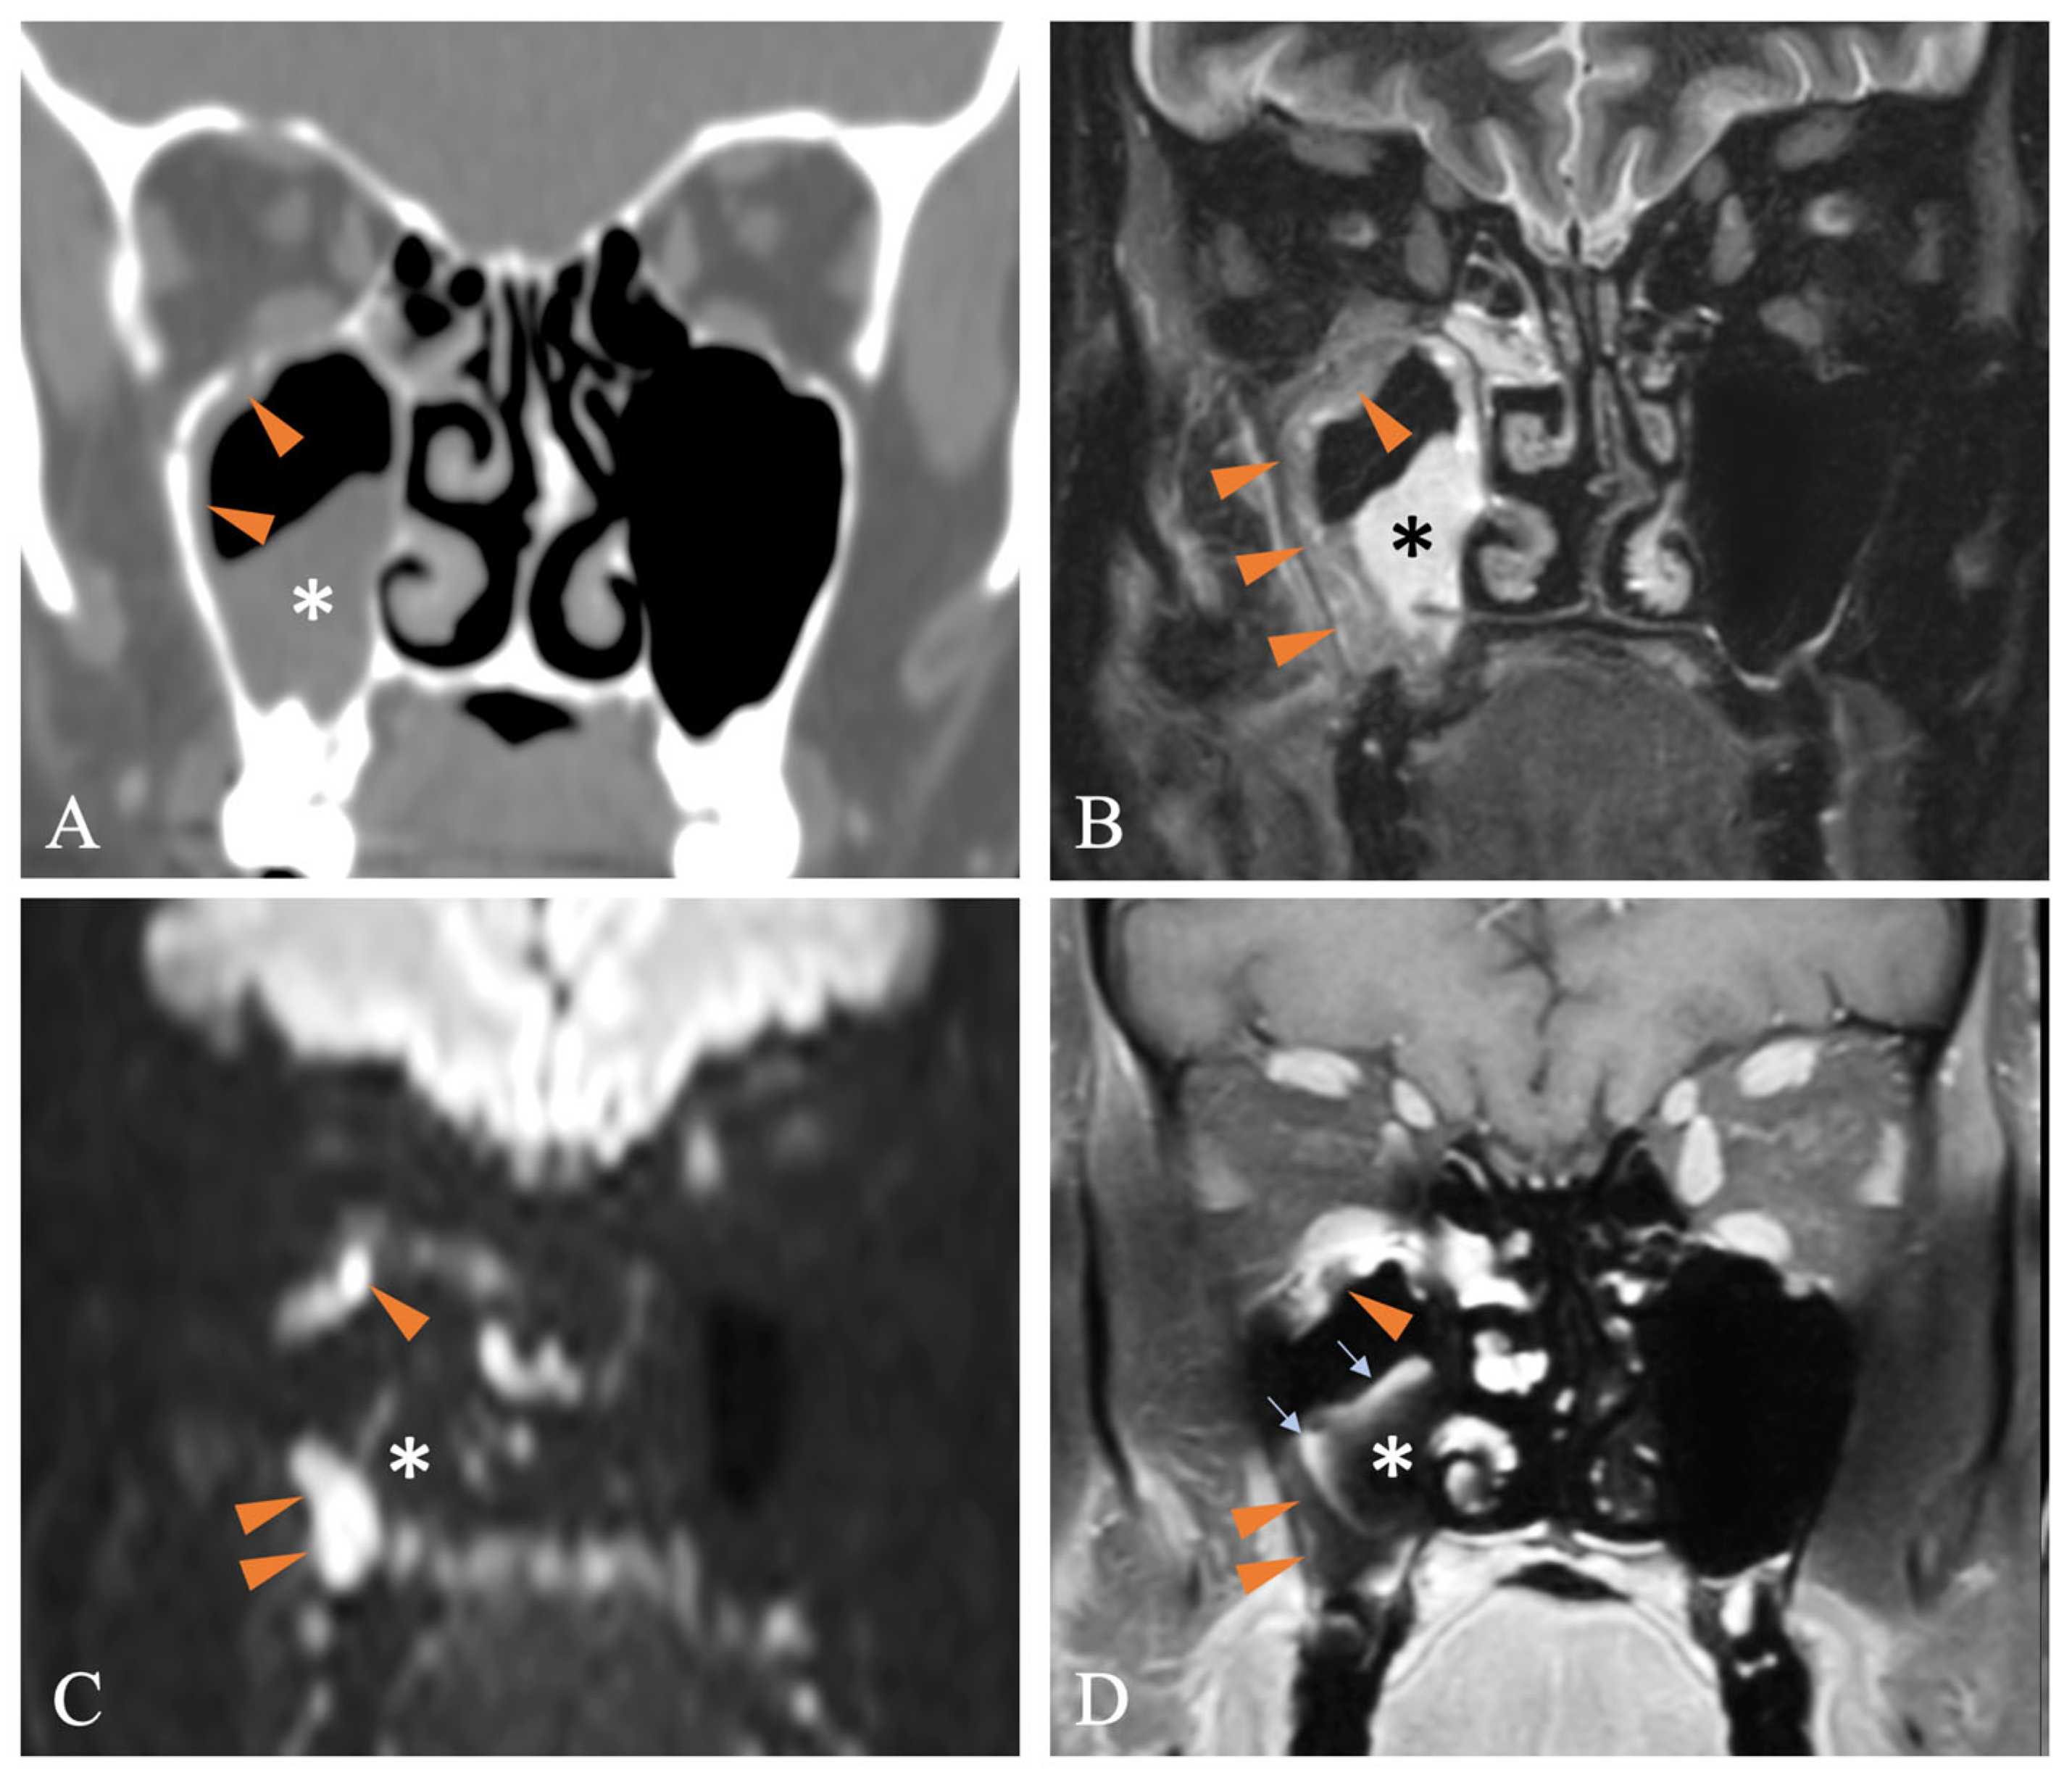

- Hassan, R.M.; Almalki, Y.E.; Basha, M.A.A.; Gobran, M.A.; Alqahtani, S.M.; Assiri, A.M.; Alqahtani, S.; Alduraibi, S.K.; Aboualkheir, M.; Almushayti, Z.A.; et al. Magnetic Resonance Imaging Features of Rhino-Orbito-Cerebral Mucormycosis in Post-COVID-19 Patients: Radio-Pathological Correlation. Diagnostics 2023, 13, 1546. [Google Scholar] [CrossRef] [PubMed]

- Middlebrooks, E.H.; Frost, C.J.; De Jesus, R.O.; Massini, T.C.; Schmalfuss, I.M.; Mancuso, A.A. Acute Invasive Fungal Rhinosinusitis: A Comprehensive Update of CT Findings and Design of an Effective Diagnostic Imaging Model. AJNR Am. J. Neuroradiol. 2015, 36, 1529–1535. [Google Scholar] [CrossRef] [PubMed]

- Silverman, C.S.; Mancuso, A.A. Periantral soft-tissue infiltration and its relevance to the early detection of invasive fungal sinusitis: CT and MR findings. AJNR Am. J. Neuroradiol. 1998, 19, 321–325. [Google Scholar] [PubMed]

- Kim, J.H.; Kang, B.C.; Lee, J.H.; Jang, Y.J.; Lee, B.J.; Chung, Y.S. The prognostic value of gadolinium-enhanced magnetic resonance imaging in acute invasive fungal rhinosinusitis. J. Infect. 2015, 70, 88–95. [Google Scholar] [CrossRef]

- Dixit, R.; Gupta, A.; Prakash, A.; Pradhan, G.S. Magnetic resonance imaging of rhino-orbito-cerebral mucormycosis: A pictorial review. Acta Radiol. 2023, 64, 1641–1649. [Google Scholar] [CrossRef]

- Safder, S.; Carpenter, J.S.; Roberts, T.D.; Bailey, N. The “Black Turbinate” sign: An early MR imaging finding of nasal mucormycosis. AJNR Am. J. Neuroradiol. 2010, 31, 771–774. [Google Scholar] [CrossRef]